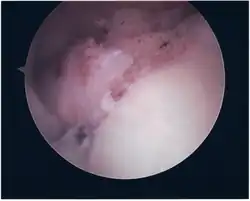

Surgical treatment of SLAP tears has become more common in recent years. The success rate for repairing isolated SLAP tears is reported between 74-94%.[10] While surgery can be performed as a traditional open procedure, an arthroscopic technique[11] is currently favored being less intrusive with low chance of iatrogenic infection.[12]

Following inspection and determination of the extent of injury, the basic labrum repair is as follows.

- The glenoid and labrum are roughened to increase contact surface area and promote re-growth.

- Locations for the bone anchors are selected based on number and severity of tear. A severe tear involving both SLAP and Bankart lesions may require seven anchors. Simple tears may only require one.

- The glenoid is drilled for the anchor implantation.

- Anchors are inserted in the glenoid.

- The suture component of the implant is tied through the labrum and knotted such that the labrum is in tight contact with the glenoid surface.